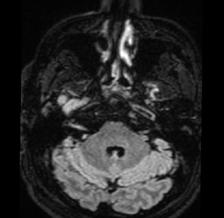

• Studiul opacifierii ramurilor corticale ale arterelor cerebrale medii (M4) drepte și stângi și a venelor cerebrale interne drepte și stângi (Fig.1).

Fig.1 ACTMS cranio-cerebrală, recon MIP în plan axial (a,b) și sagital (c): aspect normal; (a) opacifierea arterelor temporale dreaptă și stângă (săgeţi); (b) opaciferea ramurilor corticale ale arterelor cerebrale medii (M4)-săgeţi albe; opaciferea venelor cerebrale interne dreaptă și stângă (săgeţi negre-b și c).

Semiologie:

▶ Absența opacifierii M4 = 1 punct

▶ Opacifierea M4 = 0 punct

▶ Absența opacifierii venei cerebrale interne = 1 punct

▶ Opacifierea venei cerebrale interne = 0 puncte

• Un scor egal sau mai mare de 3 confirmă stopul circulator intracerebral. In acest caz, concluzia examinării este: „stop circulator intracerebral” care vine în sprijinul diagnosticului clinic de moarte cerebrală sau aspect ACT compatibil cu moartea cerebrală

• În caz contrar, concluzia examinării este „absența opririi circulatiei intracerebrale”, situaţie în care diagnosticul clinic de MC nu este confirmat.